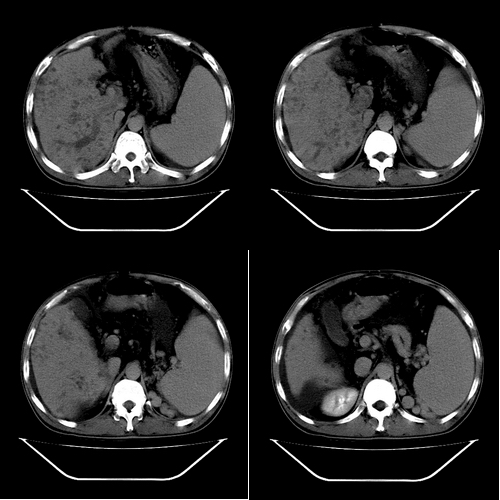

以下是引用yz在2006-6-2 12:20:00的发言:[br]肝左右叶比例失调,左叶体积明显缩小,肝边缘凹凸不平呈波浪状外观,肝左右叶可见不规则之斑片状低密度影,边界不清,以右叶为甚,肝门区增宽,增强后于动脉期病灶不均匀强化,门脉及延迟期均呈低密度,门脉主干及其右支无强化,以门脉右支明显,其内可见低密度影充填,门脉主干周围可见强化的细小侧支循环血管影。脾大,脾门血管明显增粗,脾后左侧膈脚前可见串珠状增粗强化血管影,并见胸腹水征。[br]1、考虑为弥漫性肝癌并肝门静脉主干及其右支癌栓形成,门脉海绵化。[br]2、肝硬化,脾大并门脉高压。[br]3、双侧少量胸水、腹水。